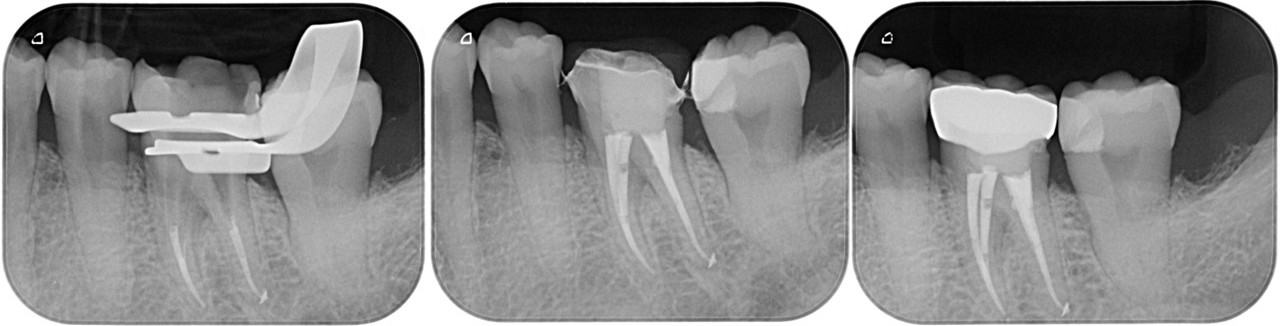

左:2018.10.29 中:2018.11.02 右:2019.02.14